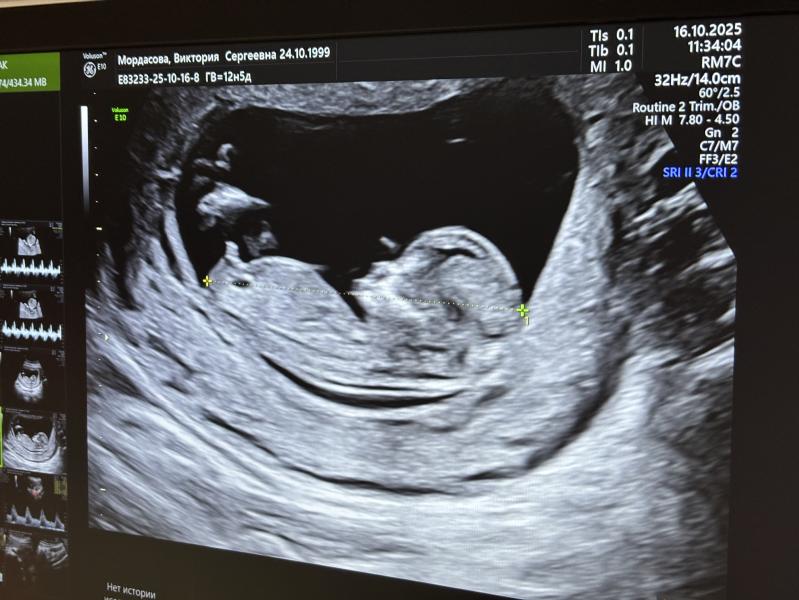

Первый скрининг пройдет 😍 Все у малышарика хорошо , срок догнал , хотя я уже не надеялась . Показали все органы , ручки , ножки . Ждем нашего сынишку 🥹

Здорово) я на самом деле удивилась , все про девочек писали , хотя почему-то появилась уверенность на сына. А муж не верил в мальчика , даже когда пипку на узи увидел 😅

@nathalie20091, с уверенность сказали мальчик. У девочек наклон другой, а тут торчек